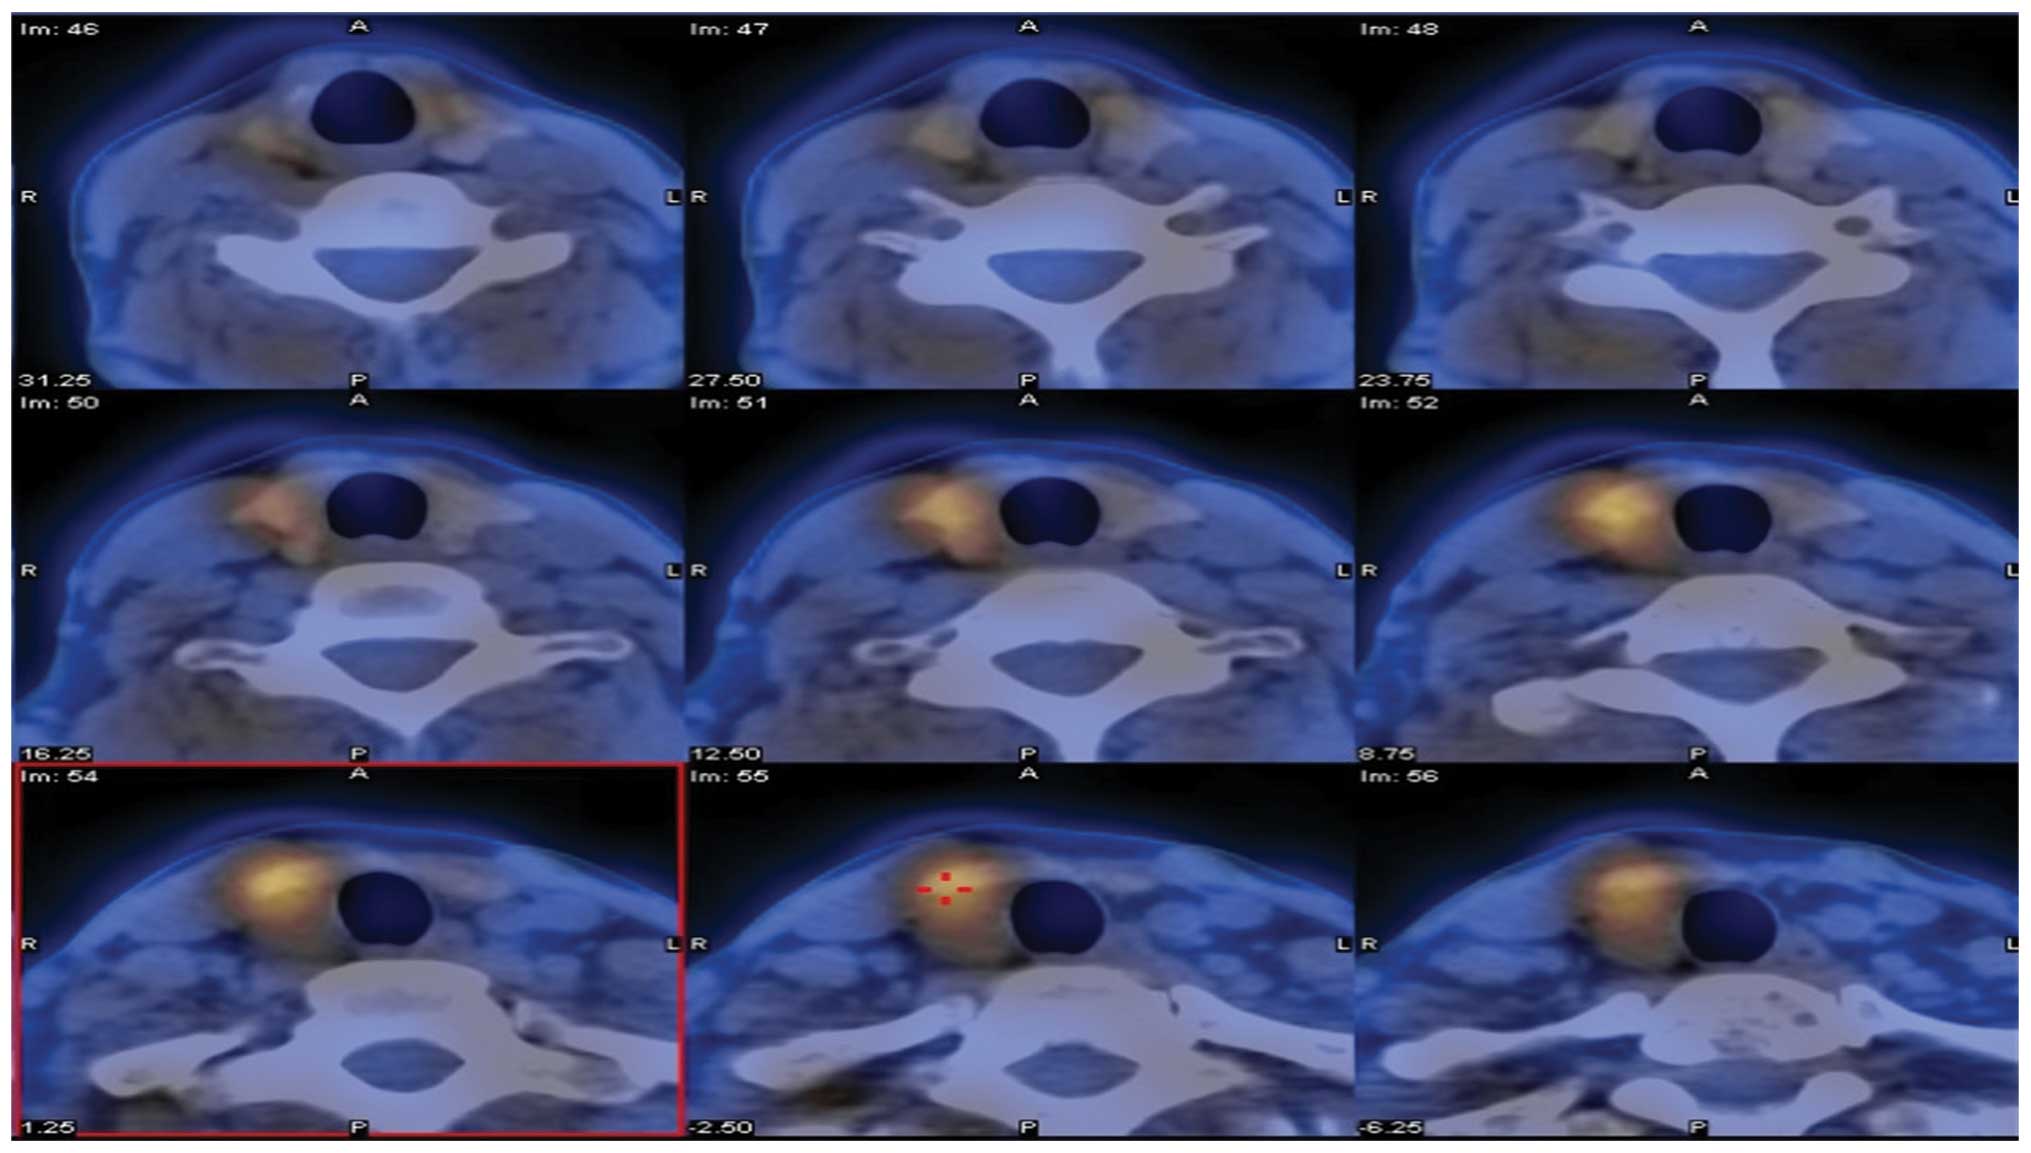

Figure 2.

Strong accumulation of Tc-99 m in the right thyroidal lobe was observed.

Sensitivity and positive predictive values

Ultrasonographic examination of the neck revealed 92 cases of occupied lesions in the parathyroid gland and 10 cases in the thyroid gland (Fig. 1). The remaining 5 cases had normal neck ultrasonography results. The sensitivity and positive predictive values were 86.0% and 95.3%, respectively. Eighty-three patients underwent Tc-99 m sestamibi scanning. The accumulation of radioactivity was observed in 75 of these patients (Fig. 2). The sensitivity and positive predictive values were 90.4% and 94.1%. The combination of an ultrasound and 99 m Tc-sestamibi scan localized hyperfunctioning parathyroid in 76/82 patients (92.7%). The sensitivity in identifying parathyroid tumors by CT and MRI was 80.8% and 79.6%, respectively (Table I).